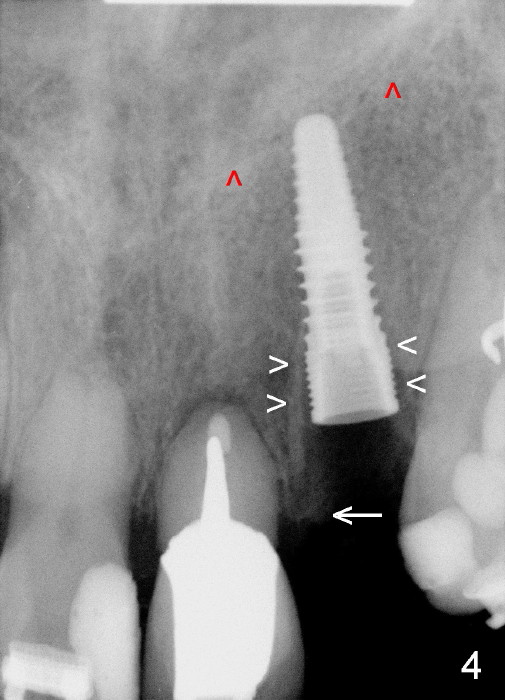

A prominent feature of implant failure in this case is pain. The patient feels that the pain is from the base of the nose. PA taken 3 days postop shows that the implant is inferior to the nasal floor (Fig.2 red ^). Clinically, the buccal gingiva continues to be erythematous 10 days postop (Fig.1). The pain is so unbearable that the implant (3.8x14 mm) is removed 10 days post placement. After repeated debridement, a 4.1 mm tap (Fig.3 T) is manually inserted with torque. A 4.1x14 mm submerged implant is placed with insertion torque < 30 Ncm, but it is placed subcrestally (Fig.4 <--). This time an immediate provisional is not provided. The flap is sutured. The pain disappears immediately. No infection is found 7 days postop (Fig.5). However, an asymptomatic vesicle is noted at the crest 3 weeks postop (Fig.6). The gingiva looks normal 2 and 3 months postop (Fig.7,8). The coronal gap dissolves 3 months postop (Fig.9 >, as compared to Fig.4), suggesting osteointegration. The implant is uncovered 4 months postop (Fig.10). Bracket is placed 5 months postop (Fig.10'). One month later, the left central incisor improves in position coronocervically (Fig.11), but the overjet needs correction by distalization of the upper anterior teeth. The implant at the site of #10 may be used as an anchorage.